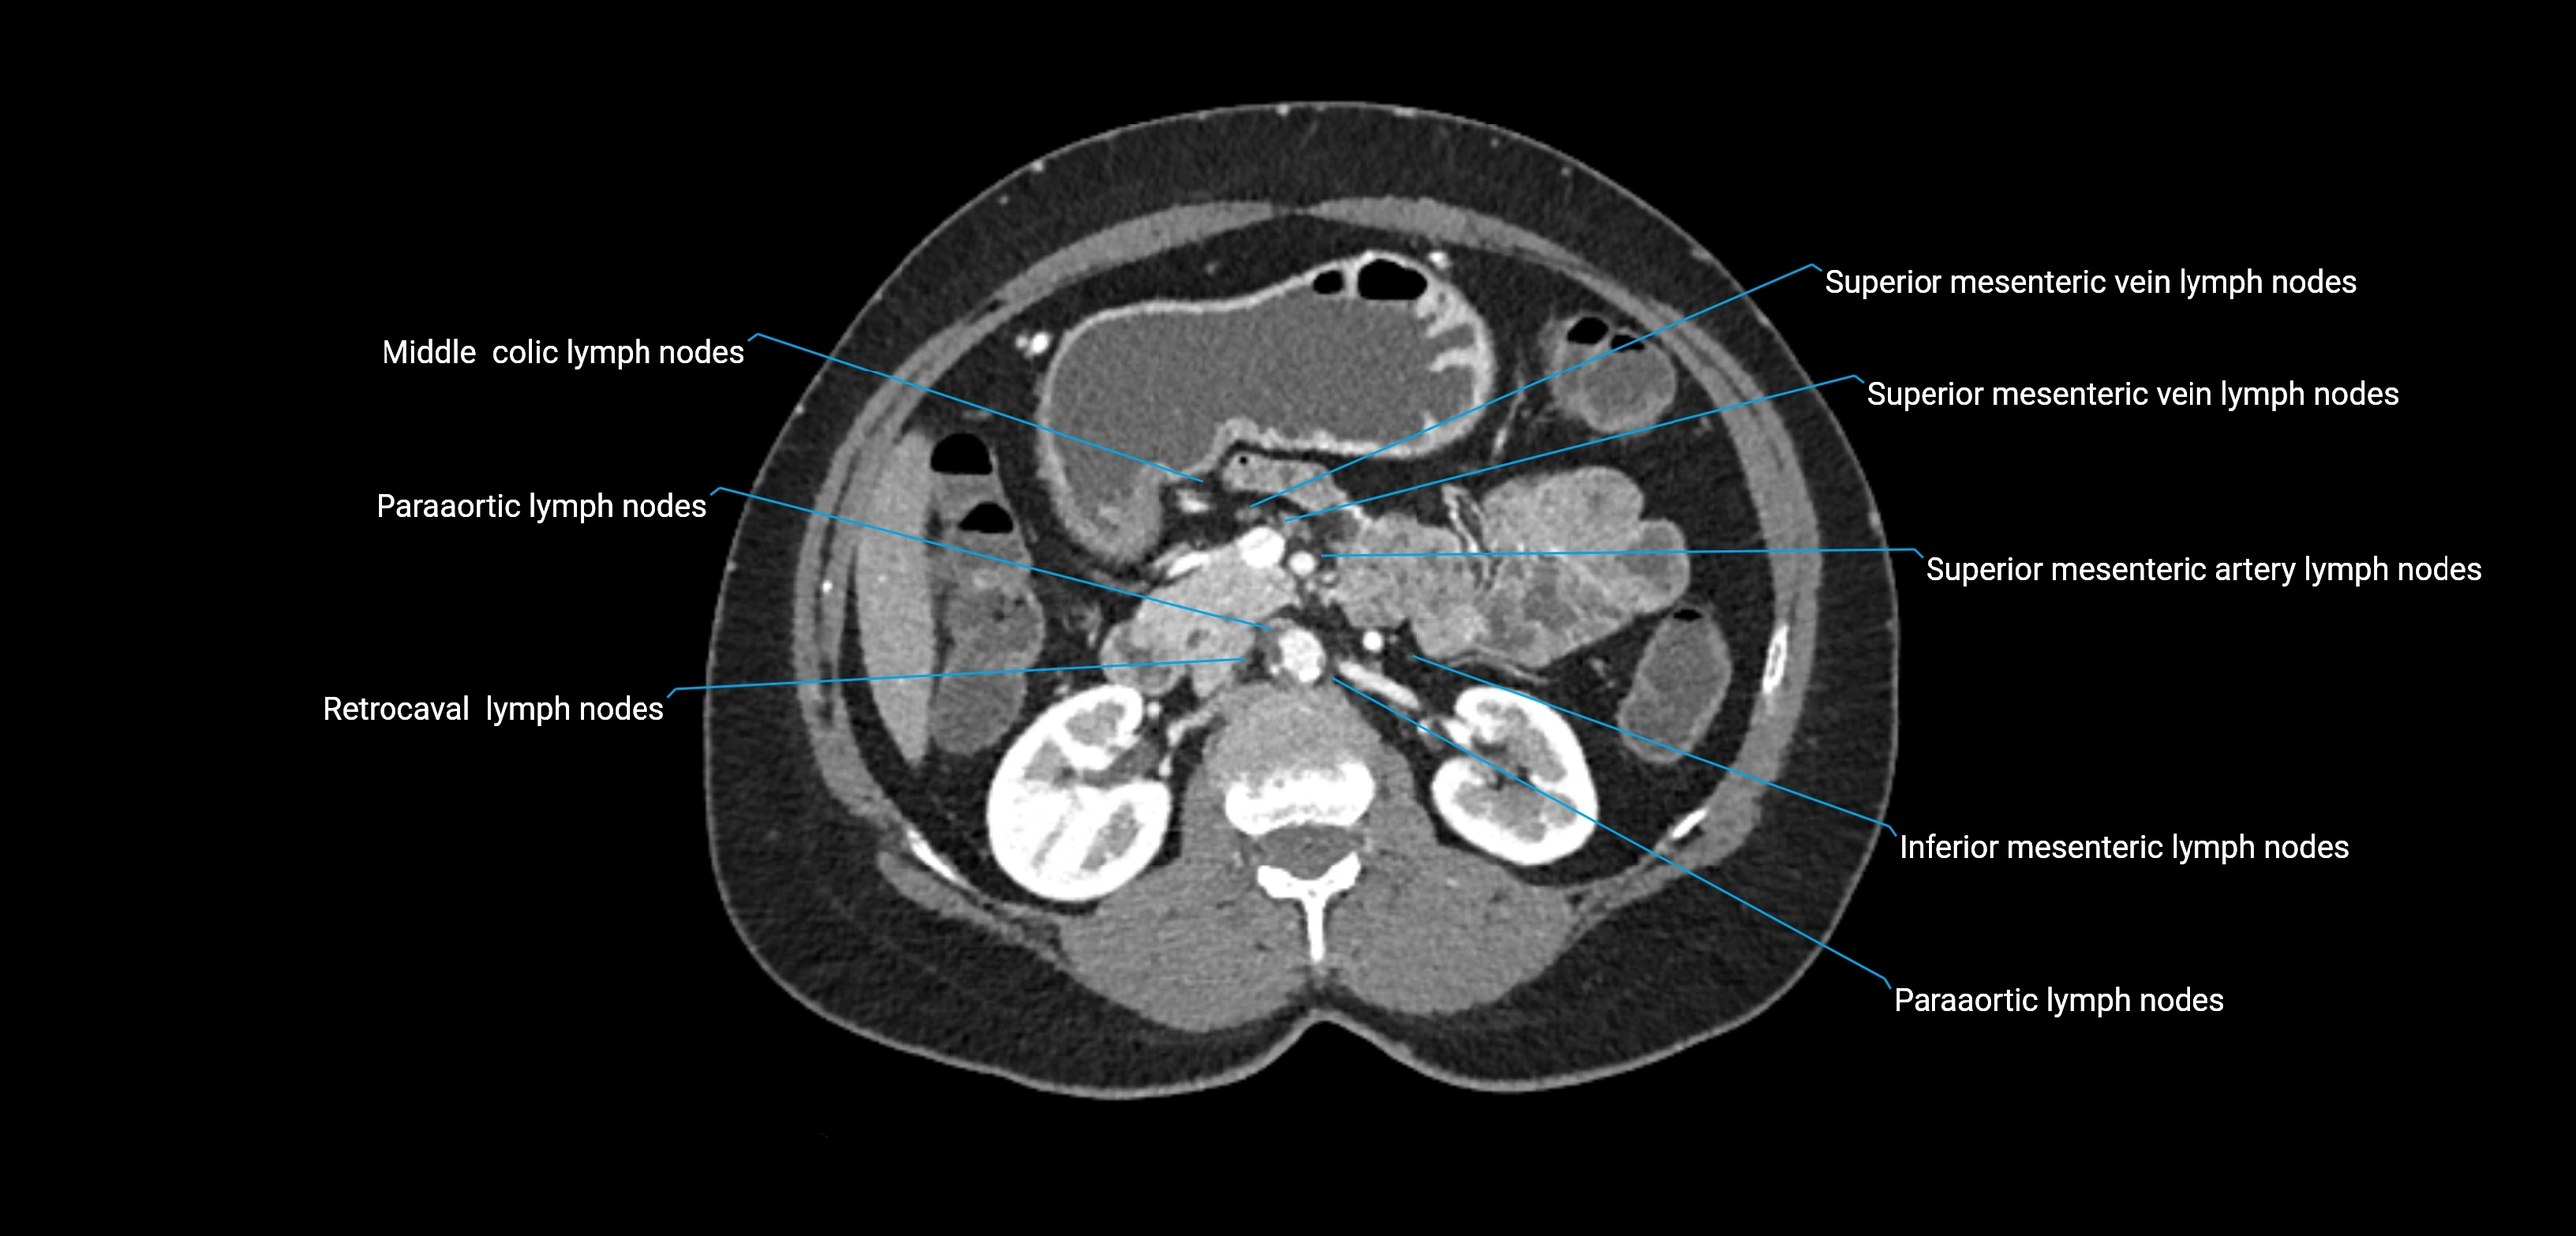

The lateral aortic lymph nodes (also called para-aortic lymph nodes) are a major group of retroperitoneal lymph nodes located along the abdominal aorta and its branches. They lie between the diaphragmatic crura superiorly and the bifurcation of the aorta at L4 inferiorly.

They are positioned on both sides of the abdominal aorta:

• Right lateral aortic nodes: adjacent to the inferior vena cava (IVC)

• Left lateral aortic nodes: lateral to the abdominal aorta

CT Appearance

CT Pre-Contrast:

• Nodes appear as soft-tissue density nodules adjacent to the aorta and IVC

CT Post-Contrast:

• Normal nodes enhance homogeneously

• Malignant nodes may show heterogeneous enhancement, central necrosis, or conglomerate formation

• Size >1 cm short axis is suspicious, though morphology and distribution are equally important

CT image

image